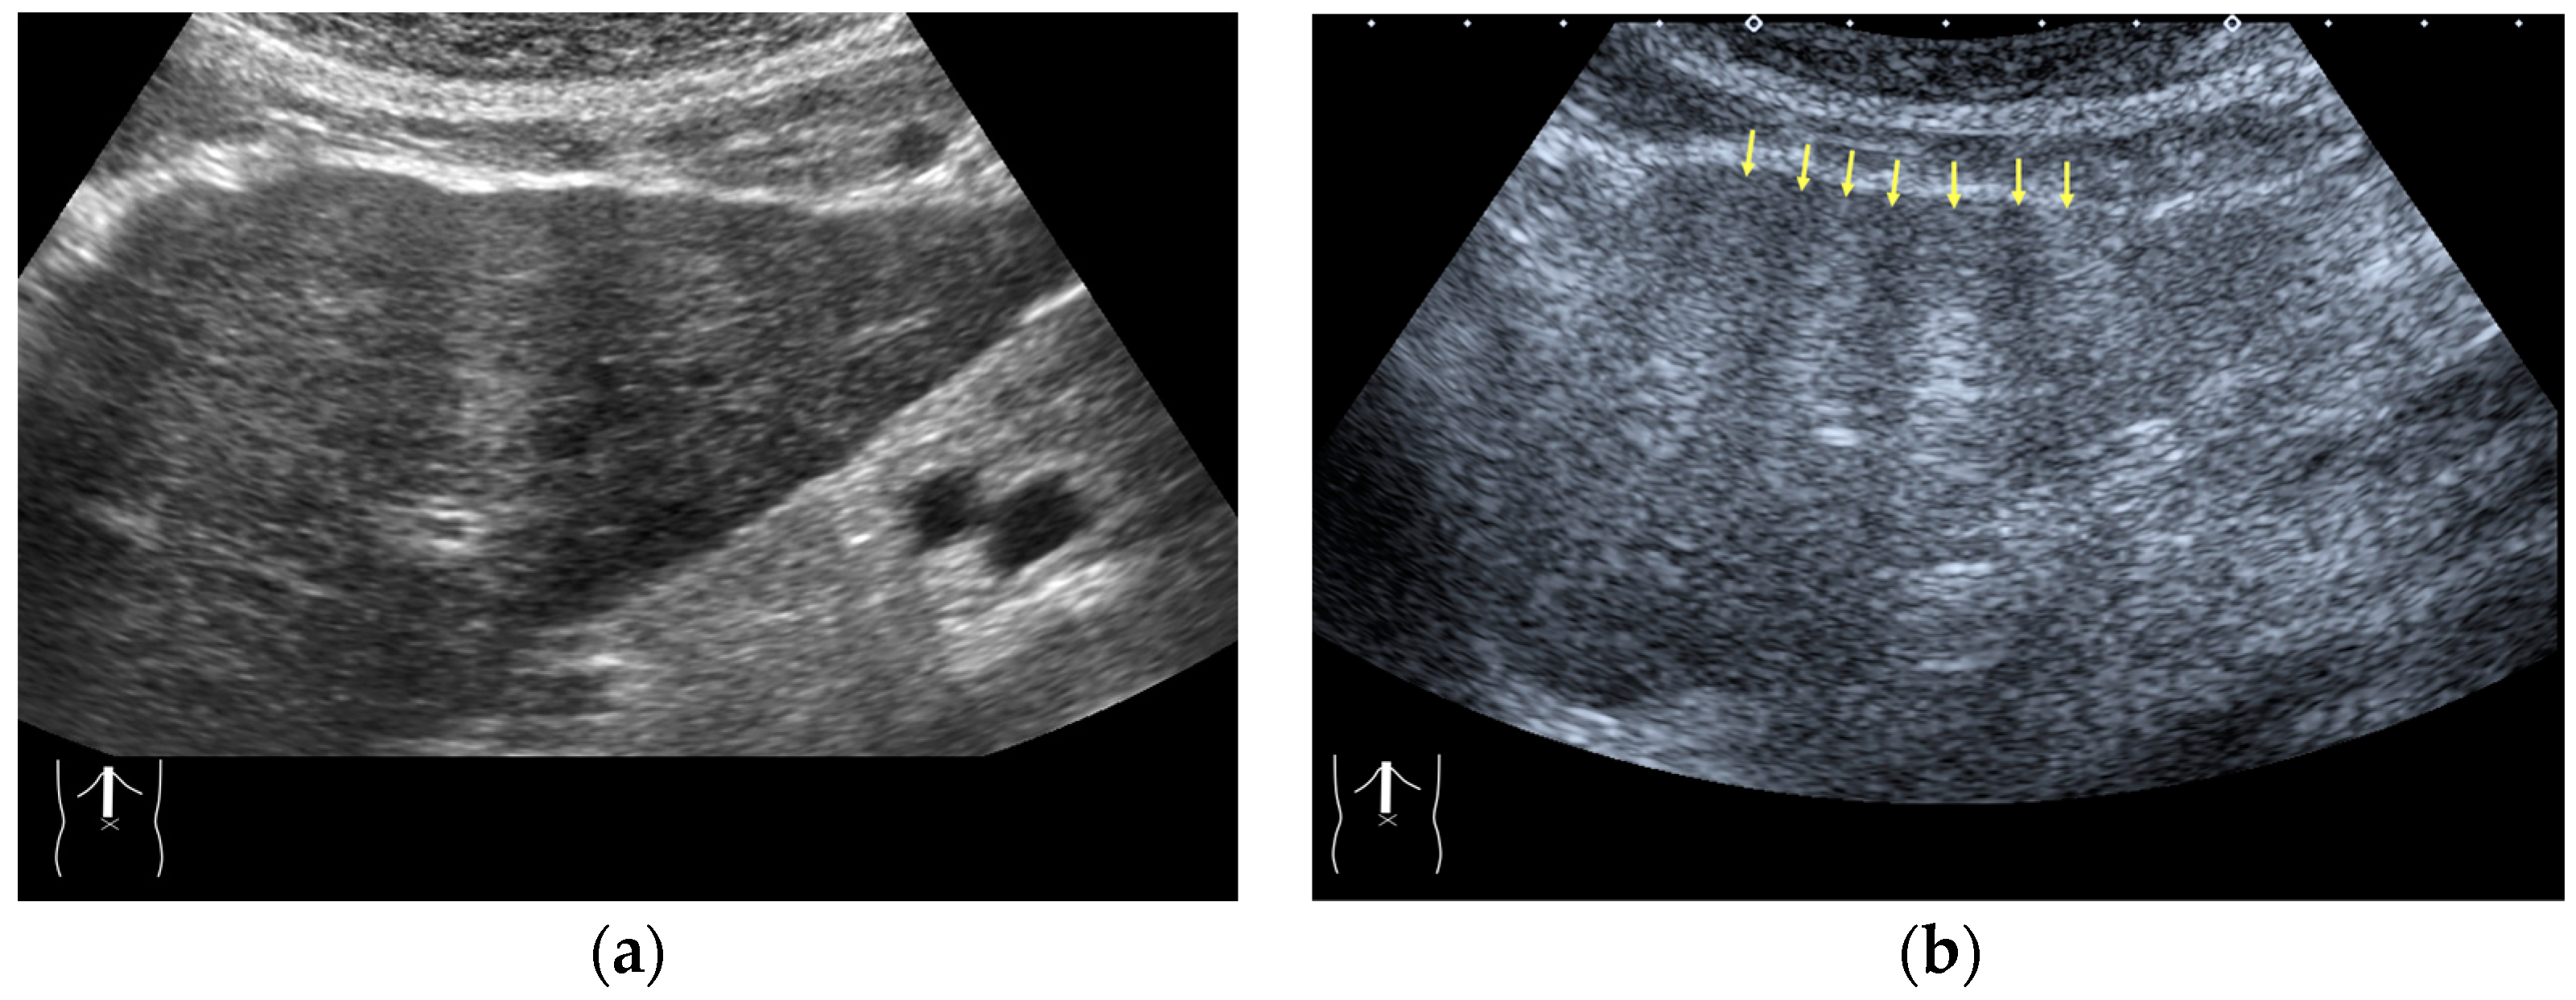

3.1.2. Attenuation Artifacts

- Naganuma, H.; Hideaki Ishida, H.; Uno, A.; Nagai, H.; Kuroda, H.; Ogawa, M. Diagnostic problems in two-dimensional shear wave elastography of the liver. World J. Radiol. 2020, 12, 76–86. [Google Scholar] [CrossRef] [PubMed]

- Naganuma, H.; Ishida, H. Factors other than fibrosis that increase measured shear wave velocity. World J. Gastroenterol. 2022, 28, 6512–6521. [Google Scholar] [CrossRef]